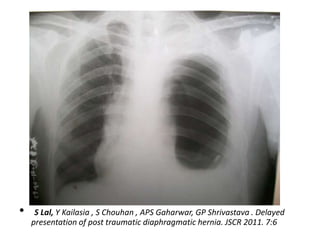

Diaphragmatic Injury

• Incidence -0.8%-1.6% in BTA

• High index of suspicion required , may be

missed.

• 40 to 50% are diagnosed immediately

• Presentation may be delayed

• Imaging

Nasogastric tube seen in the thorax

Abdominal contents in the thorax

Elevated hemidiaphragm (>4 cm Lt vs Rt)

Distortion of diaphragmatic margin.

• Lt- 69% , Rt -24% B/L- 15%

Diaphragm Rupture /Hernia

•    S Lal, Y Kailasia , S Chouhan , APS Gaharwar, GP Shrivastava . Delayed

presentation of post traumatic diaphragmatic hernia. JSCR 2011. 7:6